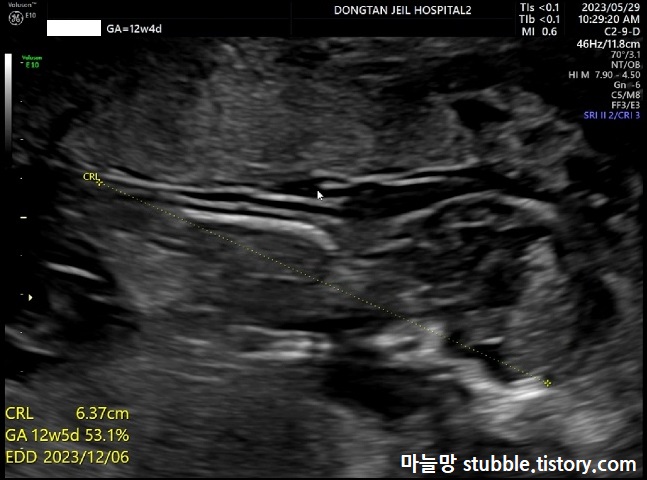

이번 초음파 사진은 병원 갈 때마다 항상 재보는 CRL이에요.

아기의 머리부터 엉덩이뼈 끝까지의 길이입니다. 우리 아기는 12주 4일 차 6.37cm입니다.

주수대비 계속 이틀이 느렸는데 이틀이 빨라졌어요. 아마도 초음파 쌤께서 아기 CRL 잴 때 아기를 반듯하게 쭈욱 펴서 재니깐 좀 더 키가 크게 나올 수 있었던 것 같아요.